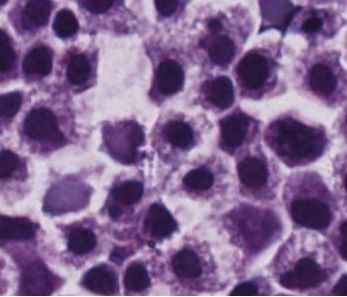

MB-102(CD123CART)是一种CAR T细胞疗法,可操纵患者的T细胞来识别和消除表达CD123的肿瘤细胞...

这种称为“嵌合体抗原受体T细胞疗法”(CAR-T)的免疫疗法从患者身上收集免疫攻击性T细胞,并对它们进行遗传修饰以识别表面上的特定肿瘤...

大多数CAR-T细胞疗法都需要靶向癌细胞特异性抗原,当前,有新方法靶向肿瘤周围的环境...